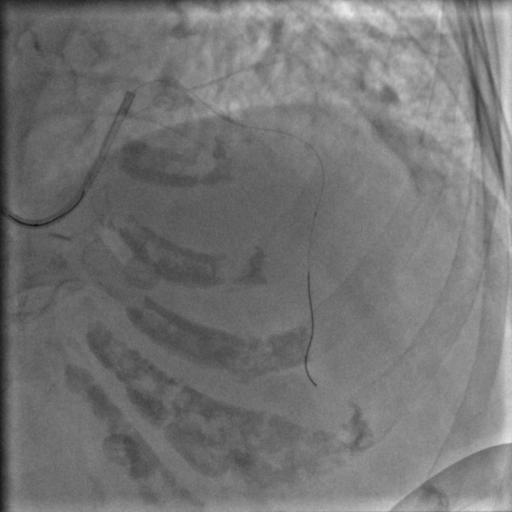

还是没通,这个也很正常。那就再拿球囊走一下,送入2.5*15mm的PTCA球囊,走得很顺,可以沿着导丝走到前降支远端,反复地走几次,看看能不能把血栓冲散,造影:

图8

还是没通,那就要来个血栓抽吸导管了,把球囊退出来,送入血栓抽吸导管到闭塞段,开始抽吸,一管、两管、三管,好了,看起来抽出来注射器里面都是血栓,抽吸的过程中似乎出现了一过性的心率变慢,应该是再灌注心律失常,应该通了吧,造影:

图9

好像前降支的显影是比刚才多出来一小节,然而依然还没通,那拿个球囊扩一下吧,把刚才的球囊送到闭塞段,2、4、6个大气压,轻轻扩一下,再轻轻扩一下,好松开,再打点硝酸甘油,造影:

图10

额滴神呐,还不通,老婆婆一直在台上痛苦地*吟呻**,我们也很揪心。再打点欣维宁吧,86岁了不能打多,再给7ml,再送入血栓抽吸导管,抽吸,依然可以看到注射器里面抽出来好多血栓,好,造影:

救命,我们已经快要绝望了,刚刚好不容易搞出来的那一小段,现在又堵上了。本来以为是个简单的病变,血栓怎么这么顽固。再来一次血栓抽吸,抽吸导管尽量往下送,造影: